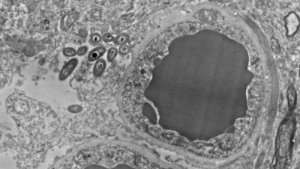

I båda studierna kunde de observera förekomsten av både hjärnorna hos människor och möss, och slå fast att det inte orsakats av infektioner eller traumatiska situationer. Faktum är att de hittade dem i flera områden i hjärnan. Främst i svarta kärnan, hippocampus samt den prefrontala hjärnbarken och väldigt lite i striaten. Ingen av hjärnorna uppvisade tecken på inflammation.

Bilder: Rosalinda Roberts, Courtney Walker, och Charlene Farmer